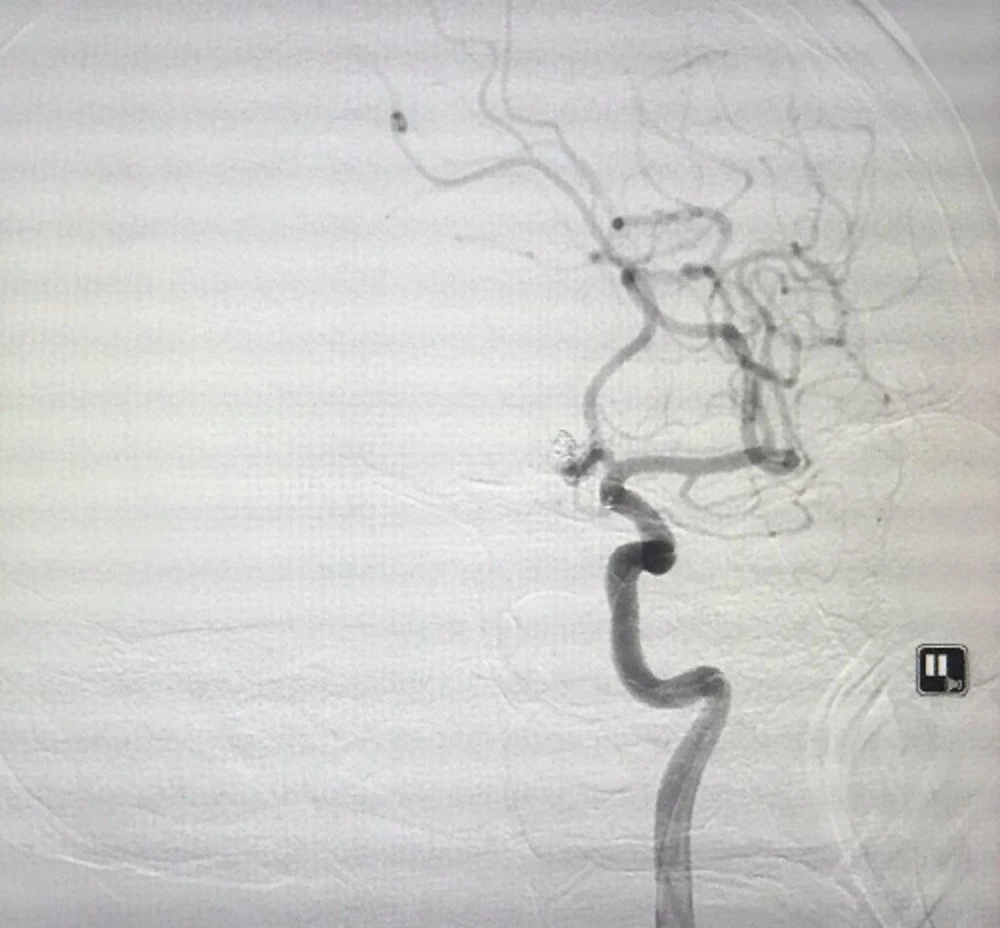

Hình ảnh túi phình đặt DSA sau khi được các bác sĩ can thiệp.

Hình ảnh túi phình đặt DSA sau khi được các bác sĩ can thiệp. Ảnh: H.P

Các bác sĩ nhận định bệnh nhân không tránh khỏi tử vong nếu không bít ngay túi phình. Tuy nhiên thực hiện thủ thuật trong giai đoạn này là hết sức nguy hiểm. Sau khi hội chẩn toàn viện và hội ý với gia đình, bệnh nhân được đưa vào phòng can thiệp lúc 21 giờ 30 để đặt coil bít túi phình mạch máu. Sau can thiệp bệnh nhân nhanh chóng tự thở được, cử động nhẹ tay chân và ngay chiều hôm sau đã có thể ăn uống, vận động được.